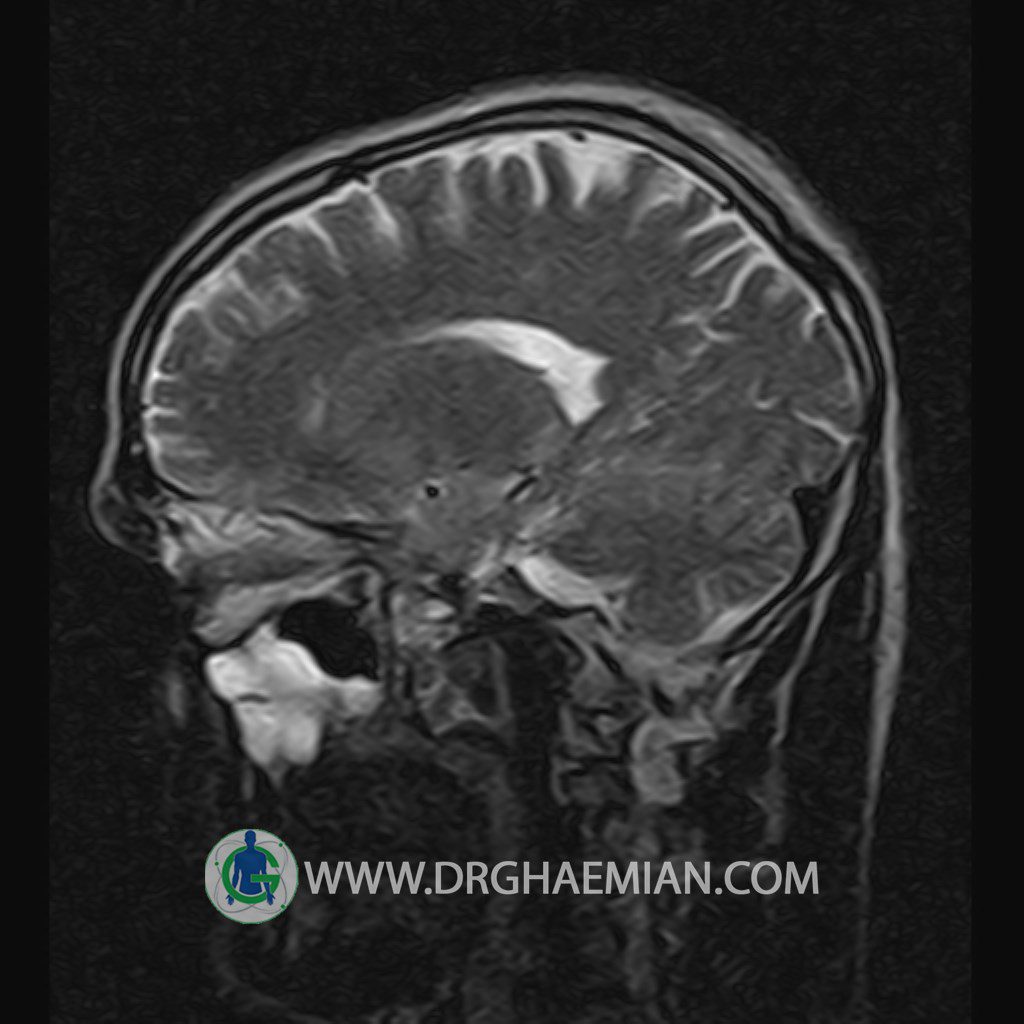

پزشکان اغلب از تصویربرداری ام آر آی برای تشخیص و درمان عارضه های پزشکی که فقط با استفاده از اشعه ایکس یا میدان مغناطیسی و امواج رادیویی قابل مشاهده است، استفاده می کنند. دستگاه ام آر آی تصاویر دقیق از ساختار های داخلی بدن ایجاد می کند. در این کیس یک میکروآدنوم در هیپوفیز بیمار مشاهده می شود.

HYPOPHYSIS MRI

(with and without contrast)

Technique: Axial , coronal T1 , Axial , coronal , sagittal T2 , Axial, coronal T1 post Gd & 64 dynamic thin coronal slices.

– Small hypoenhancing mass lesion ( 3 x 4 mm ) in posterior of pituitary stalk suggestive for micro adenoma